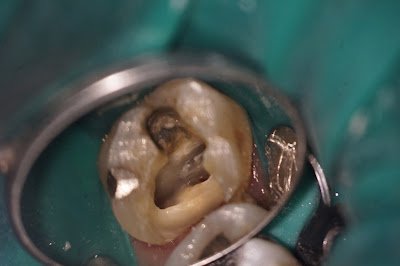

The endodontists at Superstition Springs Endodontics are partners in your patient care. One of the many ways we assist with the quality treatment of your patients in addition to endodontic diagnostics is in evaluation of restorability. With the benefit of the dental operating microscope, we are able to excavate decay and evaluate cracks in your patient’s tooth. Every crack is unique and the extent, depth, discoloration, pulpal status, patient occlusion and parafunctional habits should all be considered in the treatment planning a tooth with a crack.

Cracks that go below the cemento-enamel junction and are not able to be completely removed when the buildup is placed or completely covered by the new crown will likely affect the long term prognosis of the tooth. These types of cracks are best evaluated under the magnification of the microscope. Additional tools such at staining and transilluination are also frequently used tools in the endodontist’s evaluation of a crack.

The following case demonstrates this process and usefulness of the microscope.